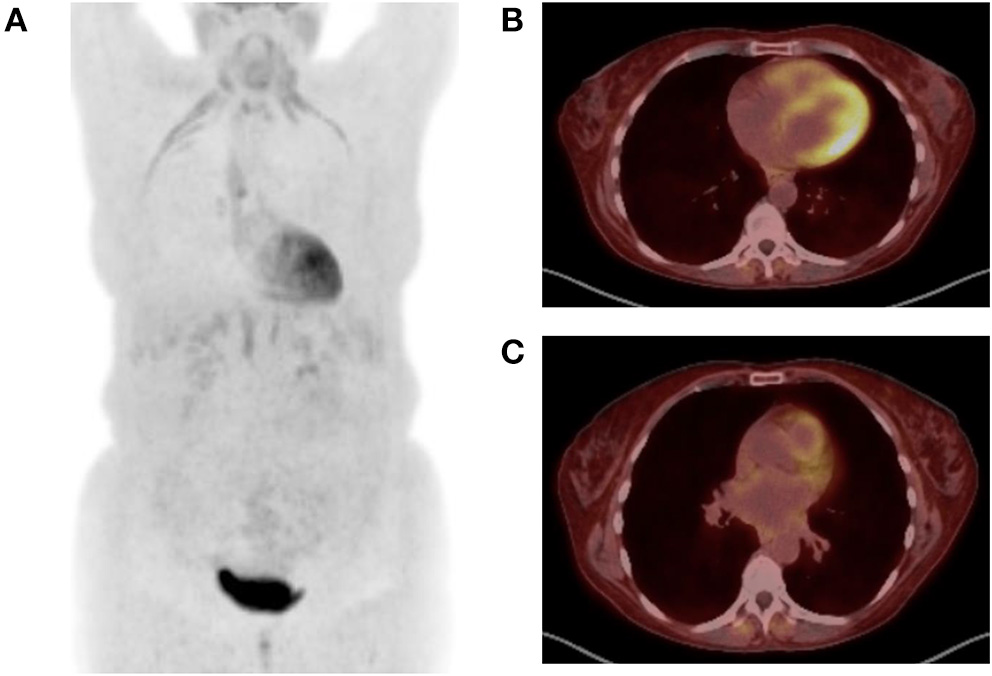

Increased stress on the right heart in PH results in an increase in myocyte glycolysis and can be measured with a radioactively tagged glucose analog and measured by PET. Increased 2-deoxy-2-[18F]fluoro-D-glucose (FDG) uptake in the RV is observed in patients with PH and correlated with mPAP (83–85). Increased FDG uptake has been found to be associated with clinical worsening and death, and patients who respond to therapy show decreased FDG uptake over time (86, 87). In addition, alternatives to FDG, such as a radiotracer targeting mannose receptors on macrophages, have been similarly observed to detect PAH and respond to pulmonary vasodilator therapy (88). Further, hybrid PET/MRI imaging has demonstrated that a combination of RV ejection fraction and tracer uptake was associated with clinical deterioration or death in PAH patients (89). Figure 3 demonstrates representative FDG-PET imaging from a PH patient with emphysema.

Figure 3

Positron emission tomography (PET) images are shown from a 52-year-old woman with emphysema and associated Group 3 pulmonary hypertension presenting with acute exacerbation. 9.78 mCi 18F-FDG injected at 119 mg/dl blood glucose level. Image acquisition 57 mins post injection. (A) Maximum intensity projection image demonstrates FDG uptake in the diaphragm, infrahyoid muscles, and intercostal muscles consistent with increased work of breathing noted during examination. There is also diffuse subcutaneous uptake, reflecting treatment with corticosteroids during the exacerbation. (B) Transaxial images at the midventricular level demonstrate abnormal uptake in the right ventricle. (C) Transaxial images at the level of the main pulmonary artery (mPA) demonstrate enlarged mPA and abnormal FDG uptake in the right ventricular outflow track.